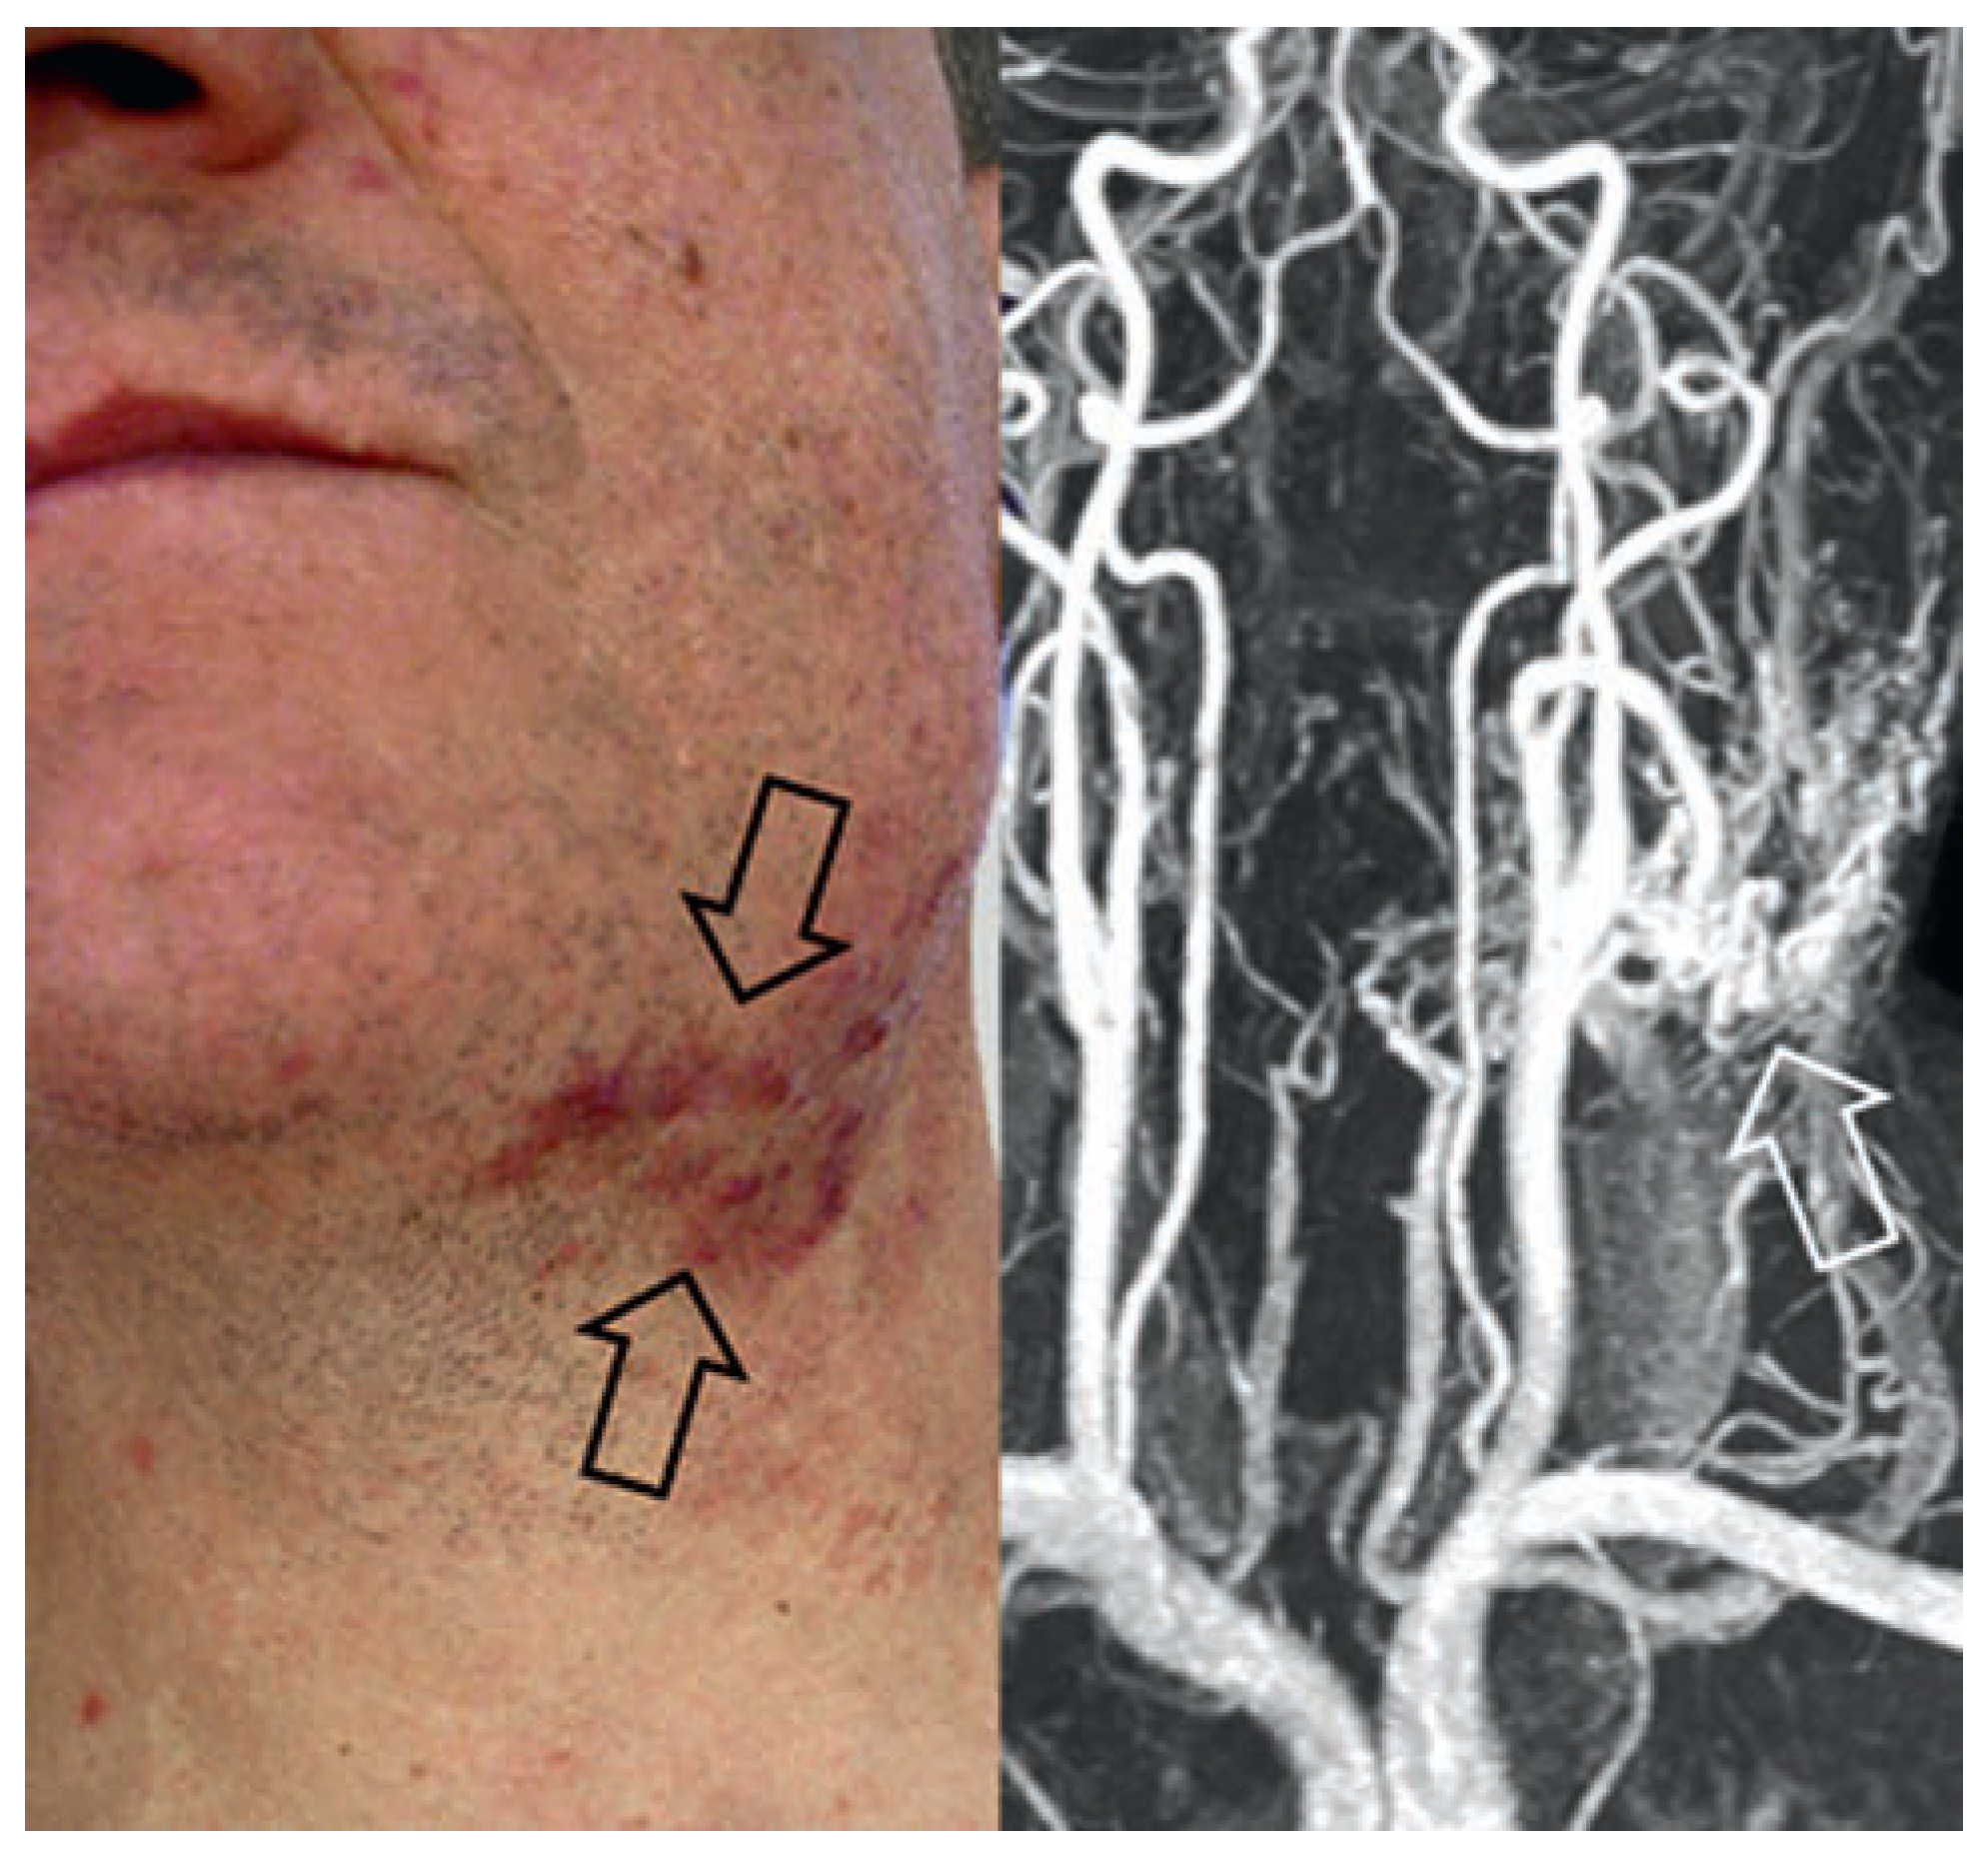

Arteriovenöse Malformation